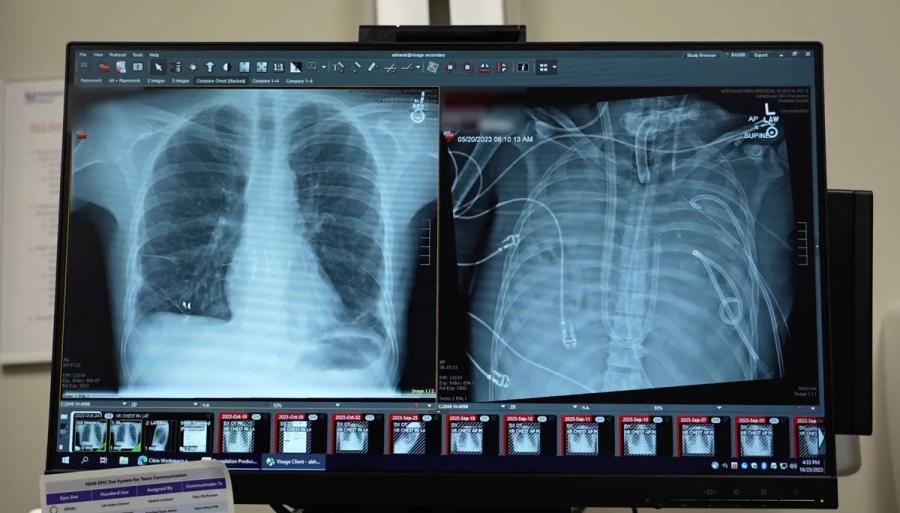

Доскоро отговорът е бил един: не можеш. В последните години обаче някои пациенти с кистозна фиброза, при които белите дробове са отказали почти напълно, са успявали да преживеят дни благодарение на изкуствени системи за оксигенация. В този случай екипът създава специална машина, способна временно да замести функцията на белите дробове — да насища кръвта с кислород, да отстранява въглеродния диоксид и едновременно с това да поддържа кръвния поток през вече отслабеното сърце.

Д-р Читару Курихара (вляво) и д-р Анкит Барат (вдясно) оперират пациент, като отстраняват увредените бели дробове и поставят изкуствен бял дроб - два дни преди самата трансплантация. Northwestern University (CC BY-SA)

Системата не е напълно ново изобретение. Технологии за изкуствено оксигениране на кръвта вече съществуват. Истинската иновация е в начина, по който лекарите предотвратяват опасното повишаване на налягането в сърцето и съдовете. Това е постигнато чрез използване на адаптивен шънт — алтернативен път за кръвта, който постоянно се нагаждал към силата на кръвния поток.

Резултатът е почти незабавен. След отстраняването на белите дробове и преминаването към външна оксигенация състоянието на останалите органи започва да се подобрява. Два дни по-късно се появяват подходящи донорски бели дробове. Хирурзите преценяват, че пациентът вече е достатъчно стабилен, и извършват трансплантацията.